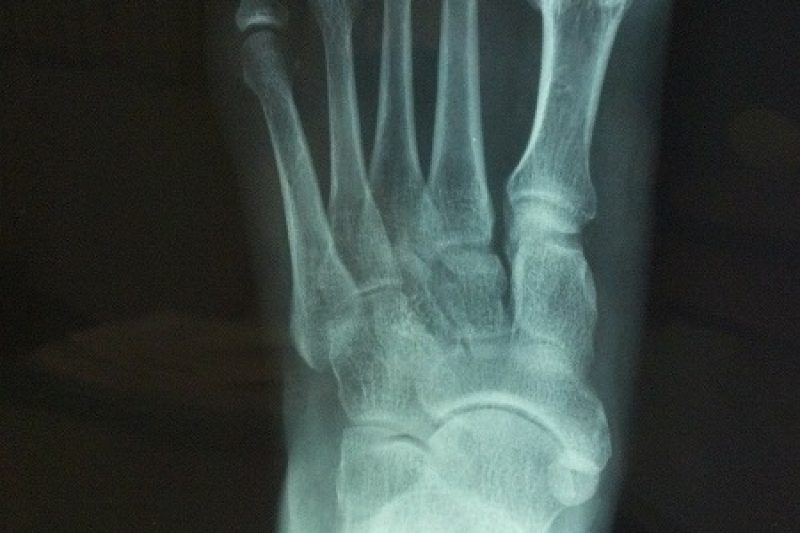

According to the American Podiatric Medical Association (APMA), 20% of Americans experience at least one-foot problem every year. This is no surprise as the feet are designed to support …